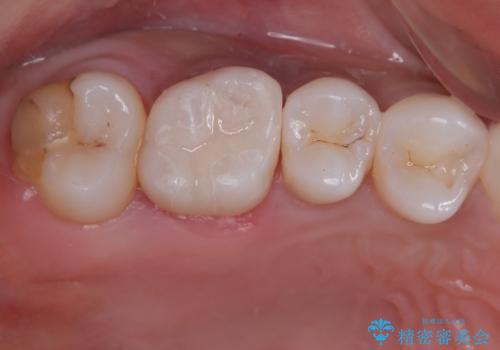

精度が高く、虫歯の再発リスクの低いゴールドインレーで治療を行うこととしました。

ゴールドインレーは適合がよいため、虫歯の再発のリスクが少ない非常に優れた材料です。

ゴールドインレーはセラミックインレーと比べ、割れるリスクが低いため、咬合力が強い方にお勧めです。